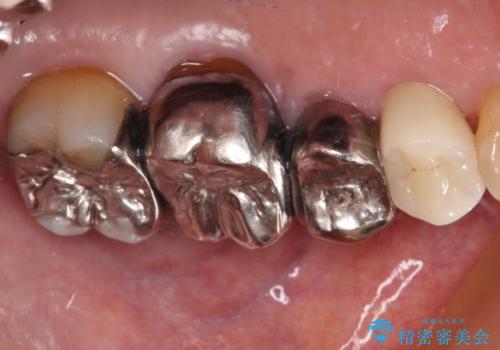

- 詰め物が欠けてしまい、虫歯かもしれないから診てほしいとのことで来院された患者様です。

精査の結果、詰め物の下に虫歯が大きく広がっているのがわかりました。

虫歯の範囲が大きく、部分的な詰め物では対応が難しいため、オールセラミッククラウンにて補綴することとしました。

また虫歯除去の際に、万一根管と交通してしまっても根管に感染を起こさないために、ラバーダム防湿をして虫歯除去しました。